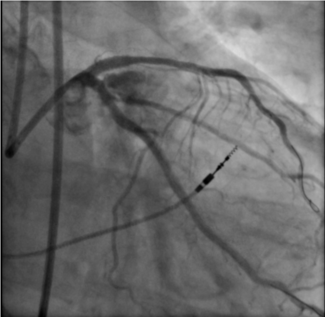

Video Supplement: Potential Alternative Mechanism of HydroDynamic Contrast Recanalization in Complete Total Occlusion Seen on DeepOCT+NIRS Imaging

Video Supplement to "Potential Alternative Mechanism of HydroDynamic Contrast Recanalization in Complete Total Occlusion Seen on DeepOCT+NIRS Imaging" (Clinical Image).

Video. Deep optical computed tomography recording of the right coronary artery after crossing the chronic total occlusion using the HydroDynamic contrast recanalization (HDR) technique. The video shows the potential mechanism of HDR, demonstrating contrast circumferentially inside the plaque and circumferential intimal dissection after balloon angioplasty of the lesion.